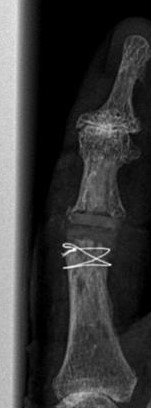

Die Röntgenbilder zeigen die implantierte Prothese im Zeigefingermittelgelenk bei gleichzeitiger Versteifung des Endgelenkes mit Schraube.

Blickfang ist hier das x-förmige Implantat zur Versteifung eines schmerzhaften und ehemals deformierten Endgelenkes.

Im Mittelgelenk fällt ein flauer "Schatten" von einem Kunstgelenk aus Silikon (Silikonendoprothese) auf.